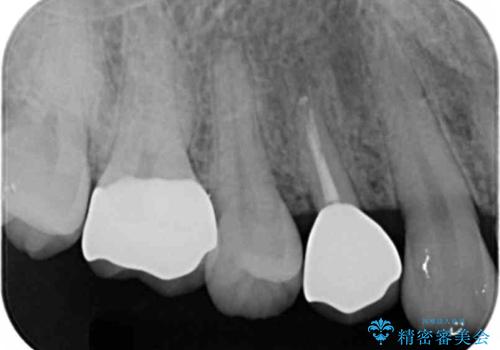

[ 深い虫歯・根管治療・セラミッククラウン ]複合した問題を持った虫歯治療

![[ 深い虫歯・根管治療・セラミッククラウン ]複合した問題を持った虫歯治療の症例 治療前](https://seimitsushinbi.jp/wp/wp-content/uploads/2022/09/b464b4c5c3053a5fc84212fb664a039f-500x350.jpg?v=1663667230)